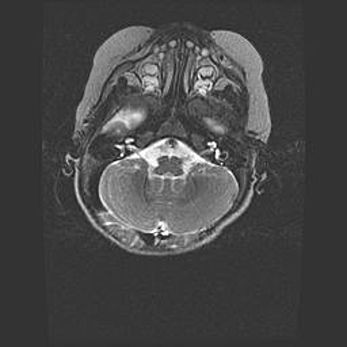

Мальформация Денди-Уокера. Киста задней черепной ямки.

Агенезия мозолистого тела.

Возраст: 2,5 месяца

Вес: 2420 г

Пол: женский

Окружность головы: 37 см

Срок гестации: 32 недели

Мальформация Денди—Уокера — редкий вид патологии ЦНС, представляющий собой врожденный порок развития каудального отдела ствола и червя мозжечка, ведущий к неполному раскрытию срединной (Мажанди) и латеральных (Лушка) апертур IV желудочка мозга. Для этогно синдрома характерна триада симптомов: гипотрофия червя мозжечка и/или полушарий мозжечка, кисты задней черепной ямки, гидроцефалия различной степени. В 70% случаев порок сочетается и с другими аномалиями головного мозга, в частности с агенезией мозолистого тела.